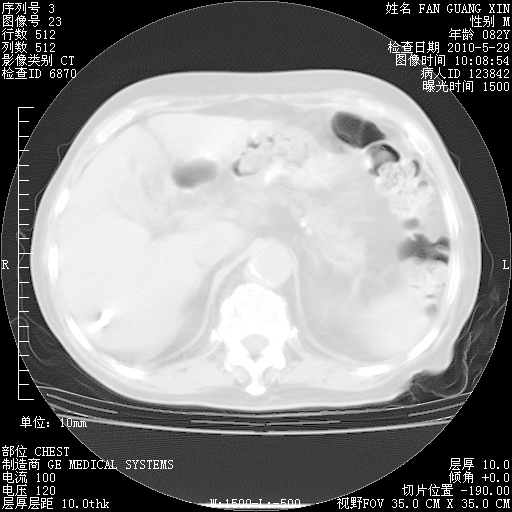

还需要哪些辅助检查?我们医院排除真菌感染没有任何检验方法,胸片好像能够排除肺部真菌感染。

补充:ENA化验全部阴性。免疫五项(IgG、IgA、IgM、C3、C4)只有C4略高。